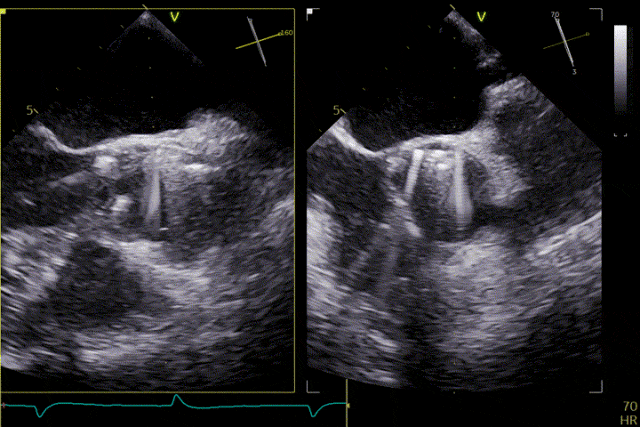

輸送器跨瓣

打開定位件

定位件入竇

瓣膜釋放